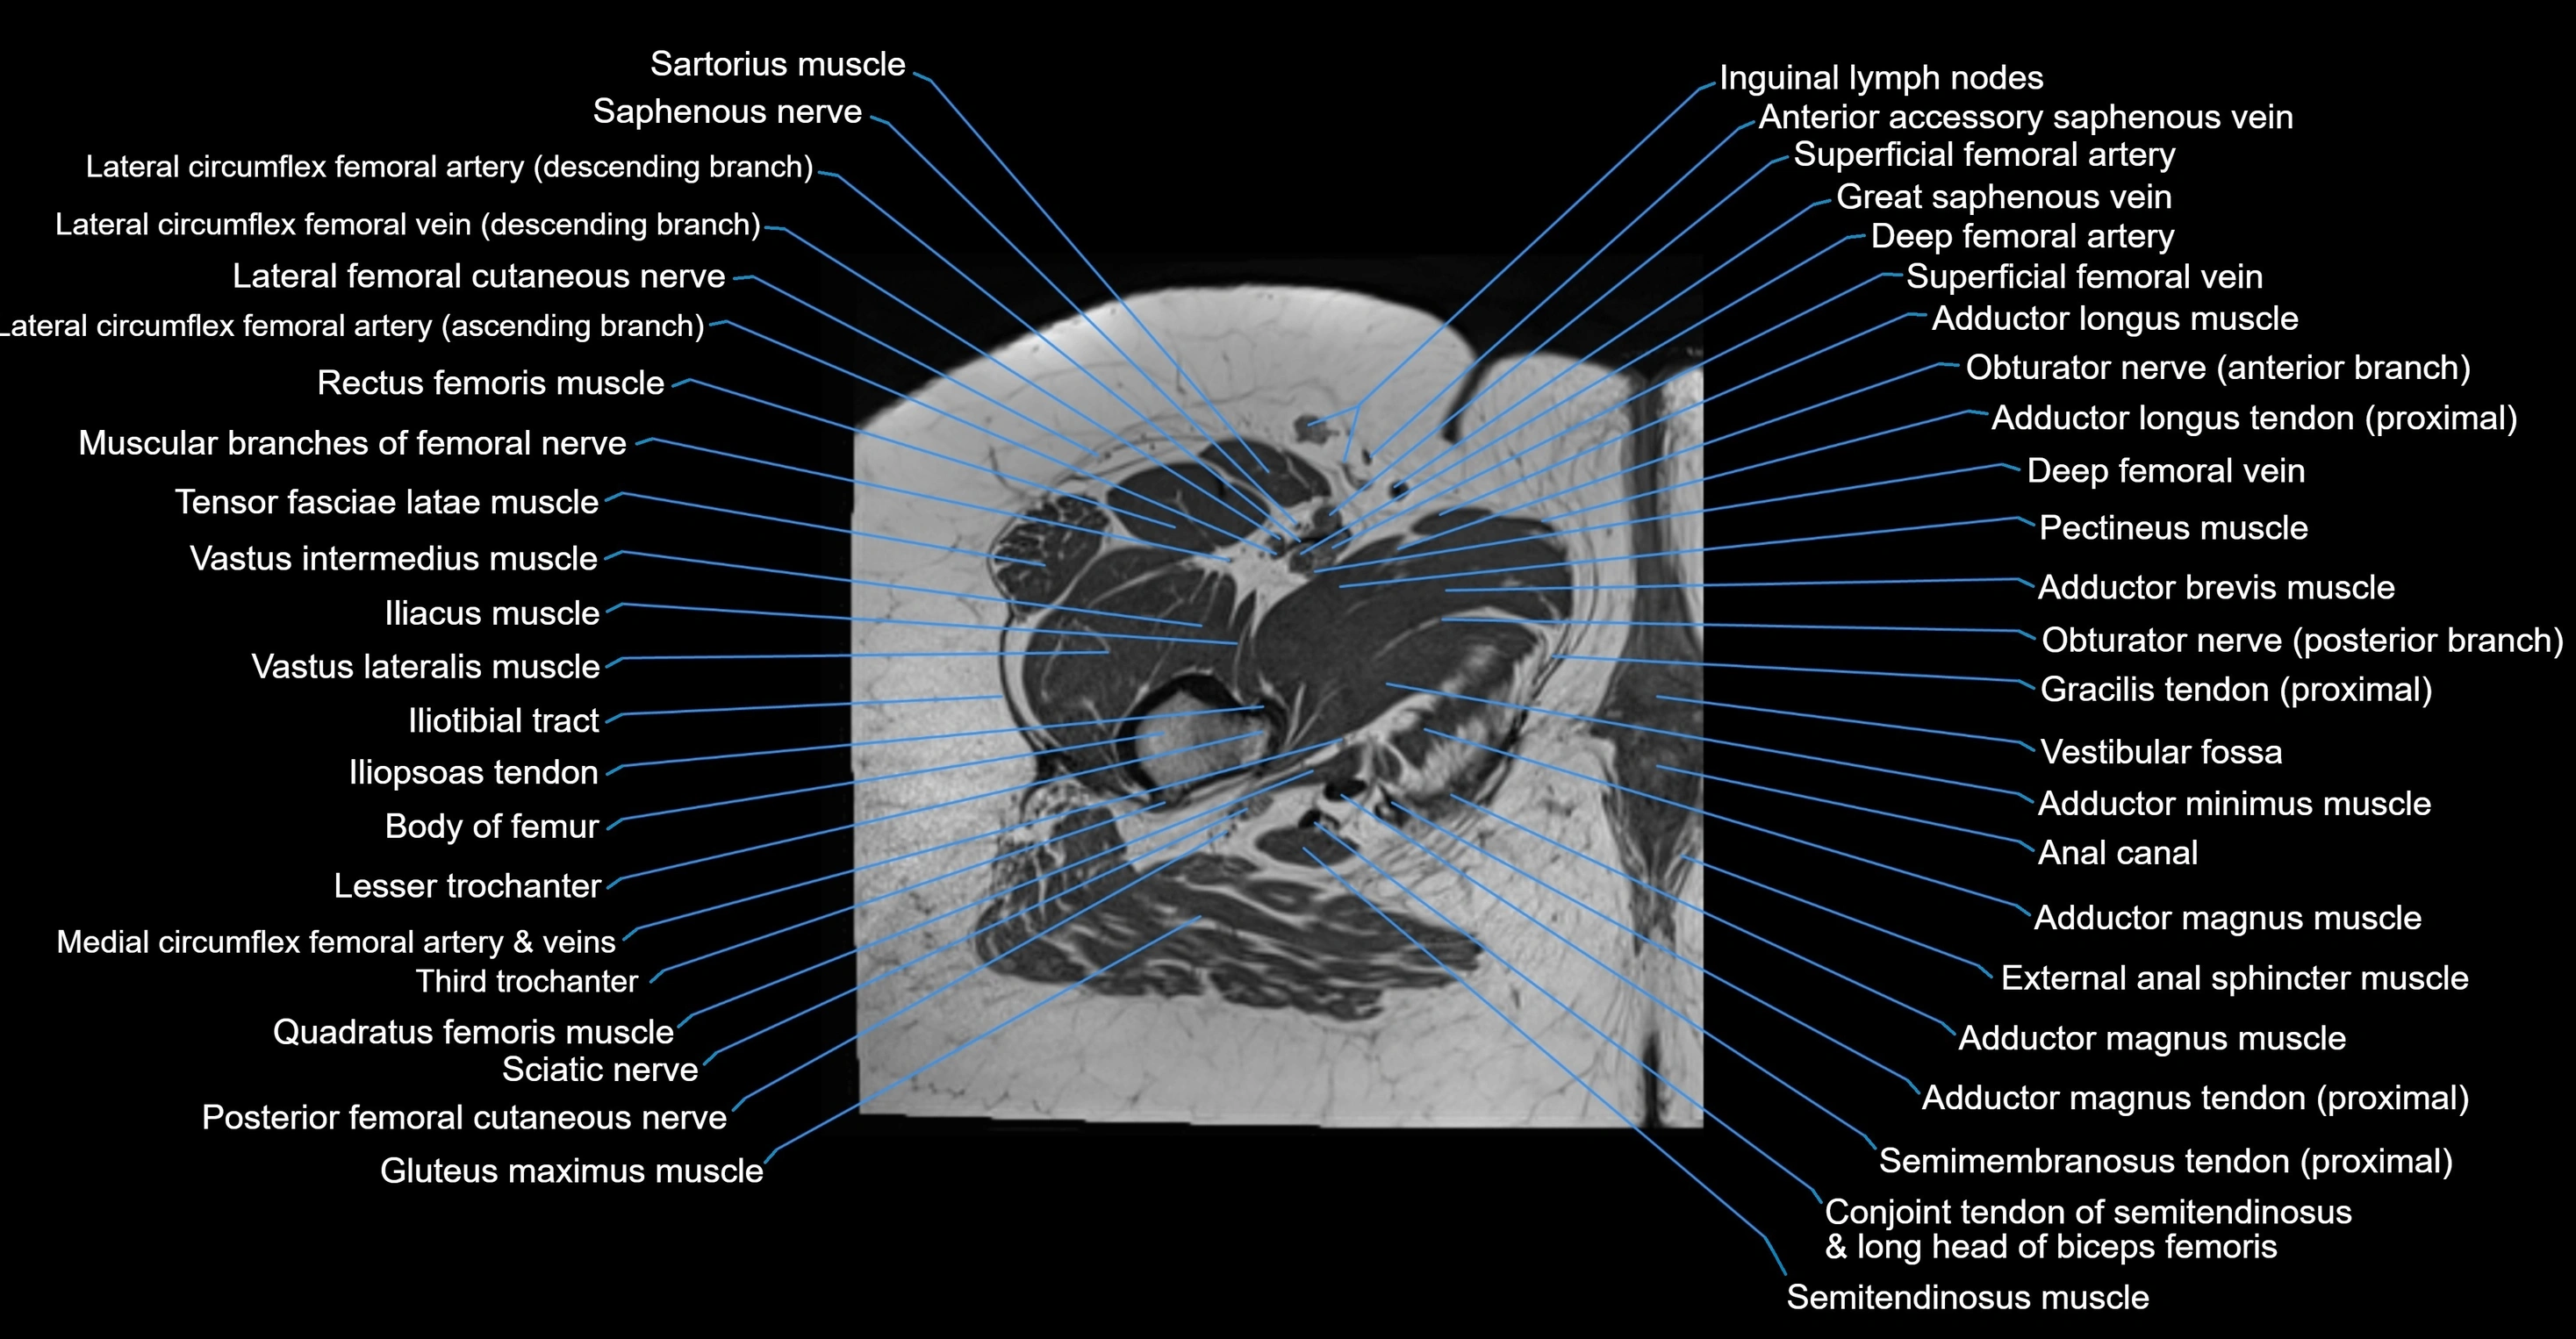

- Adductor brevis muscle

- Adductor longus muscle

- Adductor magnus muscle

- Adductor minimus muscle

- Conjoint tendon of biceps femoris & semitendinosus

- Deep femoral artery (profunda femoris)

- Deep femoral vein (profunda femoris vein)

- Femoral nerve

- Gracilis muscle

- Iliotibial tract

- Inguinal lymph nodes

- Lateral femoral cutaneous nerve

- Lesser trochanter

- Pectineus muscle

- Posterior femoral cutaneous nerve

- Quadratus femoris muscle

- Saphenous nerve

- Sartorius muscle

- Semimembranosus tendon (proximal)

- Superficial femoral artery

- Tensor fasciae latae muscle

- Third trochanter

- Vastus intermedius muscle

- Vastus lateralis muscle

- great saphenous vein